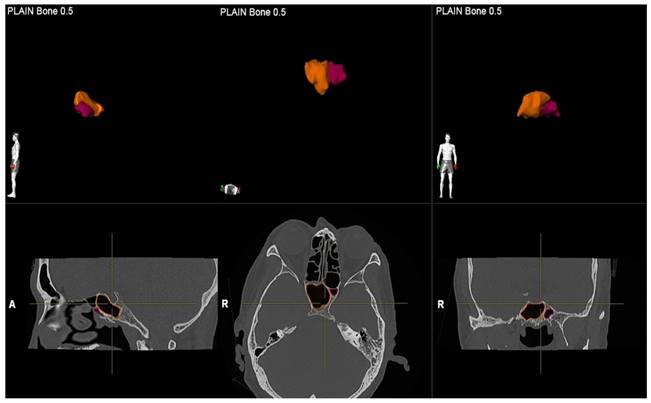

A single investigator, an otolaryngologist with more than ten years of clinical experience, performed image segmentation by measuring the volume of the sphenoid sinus. For each patient, the volume of the sphenoid sinus was measured using commercial real-time segmentation software (Elements SmartBrush, Brainlab AG, Munich, Germany) on a personal computer. The software exploits parallel implementation of a sparse field level-set solver on the Graphics Processing Unit (GPU) by implementing the level-set algorithm and has been utilised in various clinical applications such as tumour localisation and estimation of tumour dimensions [15,16]. The segmentation was achieved using a set of Hounsfield units in CT. The anatomical volumetric measurements were performed by means of this software in hand tracing. The lumen of the sinus was delineated. The lumen of the sinus was defined as the space within the bony walls of the sinus in all three planes (axial, coronal, and sagittal) (Figure 1). Within an automatically determined region of interest (ROI), segmentation was conducted by the 3D interpolation of the program itself. The software uses an inverse present method. The program reconstructs a 3D model of the sinus from the DICOM image sequence on which the volume was selected by cutting out the complementary areas of the air-filled area in the three dimensions manually; then, the volume was reconstructed and measured in cubic centimetres (cm3) by the software (Figure 2). Each side of the sphenoid sinus (right and left) were measured separately. The total sphenoid sinus volume was obtained based on the right and left sphenoid sinus volume summation. After 15 days, the measurements were repeated. All information was analysed using Statistical Package for Social Sciences (SPSS) software version 26.0.

Figure 1

Volumetric measurement of the right and left sphenoid sinus.